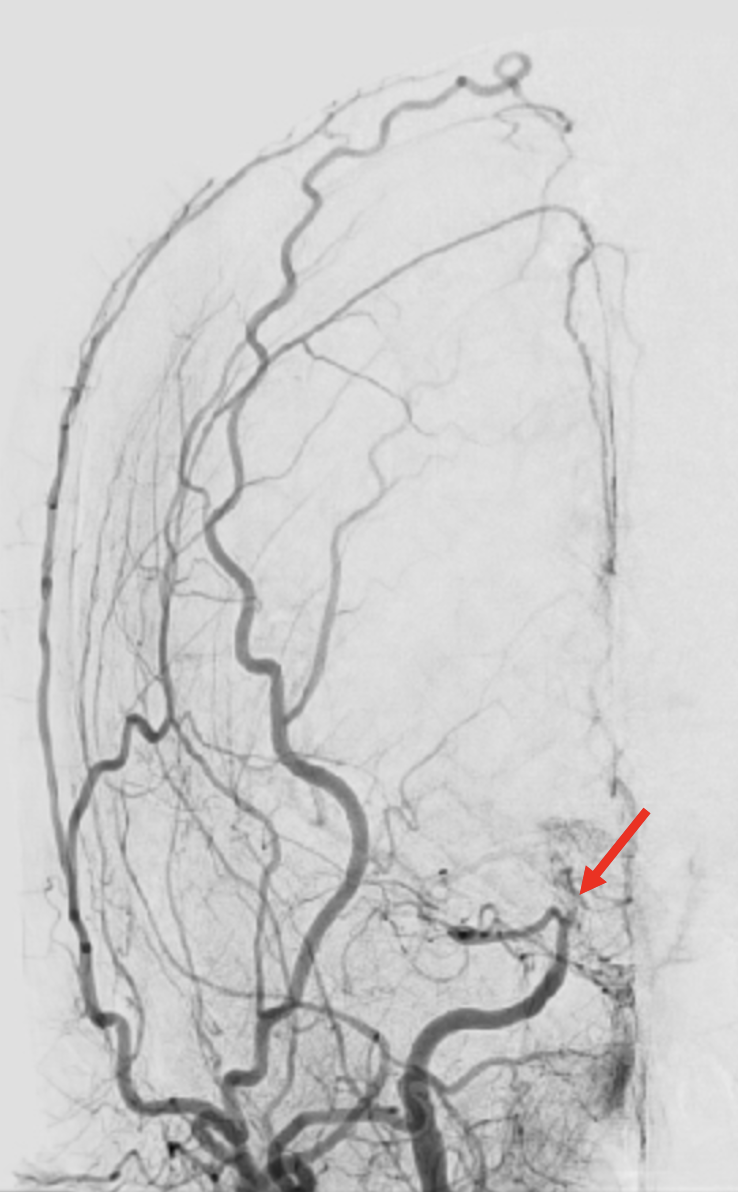

Moyamoya disease

Although uncommon, Moyamoya disease has been a focal point of research for the Brain Aneurysm Institute, driven by the inspiration drawn from numerous patients. We have conducted reviews analyzing the efficacy of revascularization, identifying risk factors for bypass failure, and scrutinizing the decision-making processes for both indirect and direct bypass procedures. Our interest extends to understanding the molecular mechanisms underlying the pathogenesis of Moyamoya disease, involving studies on genomes and blood markers to elucidate the disease cause, enhance existing treatments, and develop novel therapies.

Our research efforts are closely intertwined with the Adult Moyamoya Center at BIDMC, a comprehensive service that brings together nationally renowned experts in stroke and vascular neurology, neurosurgery, and radiology, providing state-of-the-art evaluation and treatment for adults with known or suspected Moyamoya disease. Ours is one of the most experienced groups in the nation in treating this disease in adults.